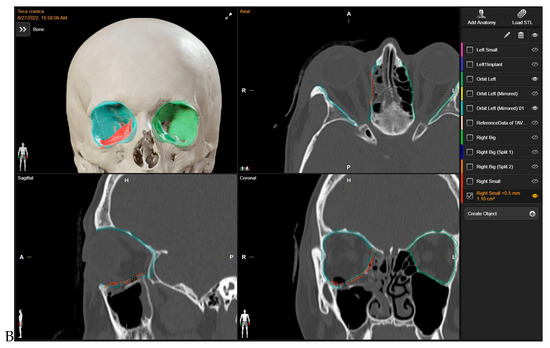

Initially, mirroring techniques were employed to achieve a virtually ideal reconstruction of the orbital defect. Subsequently, the STL file of the plate was uploaded into the Brainlab Element Software 4.0. The 3D-POTM’s STL files were digitally overlaid onto the simulated optimal 3D virtual orbital reconstruction. The software’s tools were then used to manipulate the plate object, adjusting its position within the reconstructed orbit created via mirroring. To ensure a precise fit to the boundaries of the mirroring, the “object management” tool was employed to cut the plate. This process allowed for the customization of the plate’s shape, ensuring optimal adaptation to the specific orbital defect and the mirrored orbit. In this stage, digital planning was employed to determine the required trimming of surplus mesh components, and the ideal placement for the implant was computed by two senior surgeons. This assessment drew upon the data from the STL file and preoperative scans analyzed through Brainlab Elements Contouring, version 4.0 (Brainlab, Feldkirchen, Germany). In contrast, a bending plate was not designed. The preformed meshes utilized in the study (3D Orbital Floor Plate, Stryker Corp., Kalamazoo, MI, USA) were already shaped appropriately to accurately reproduce the orbital floor and/or the transition zone between the orbital floor and medial orbital wall, without requiring bending. The estimation and verification of the implant’s location within the orbit, as well as its connections with the anatomical structures of the orbit, were subsequently confirmed (Figure 1). In all cases, presurgical VSP took place before the patient’s hospitalization, primarily in the outpatient clinic. The process of virtual planning, including the manipulation of 3D models and the determination of surgical approaches, was conducted before the hospitalization. The navigation system (Brainlab Curve, Brainlab, Munich, Germany) was loaded with both the preoperative CT scan and the STL file of the 3D-preformed implant.

Figure 1. Preoperative Virtual Planning. The 3D-preformed titanium mesh’s STL files were virtually overlaid to align with the “ideal orbital reconstruction” achieved by using the mirrored unaffected contralateral side as a reference. In red: STL files for 3D-preformed titanium mesh. Light blue: mirrored orbit. Green: safe orbit.